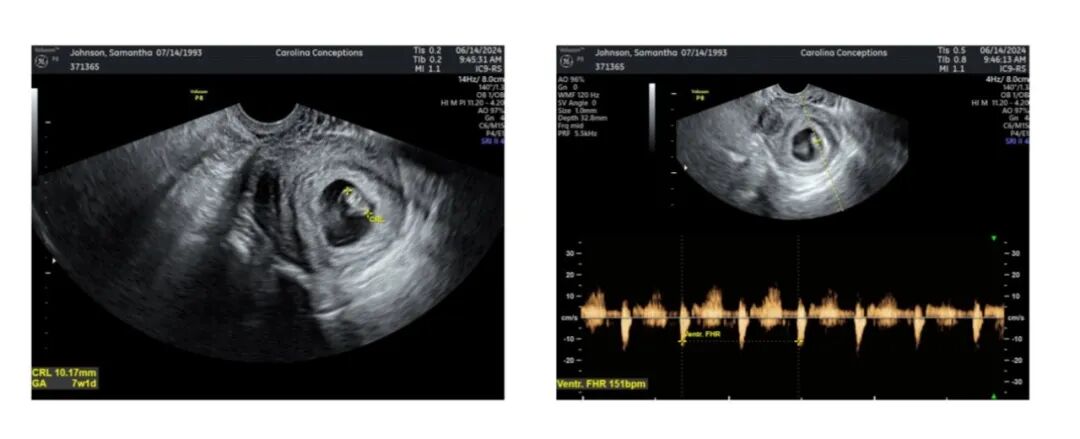

爱妈S在首次B超检查来了!已能听到宝宝强有力的心跳,尽管宝宝还很小。准父母对此感到无比激动,他们特别期待属龙的宝宝,并已成功匹配了两位代母,另一位爱妈的妊娠也在顺利进行中,满怀期待宝宝们继续健康成长。